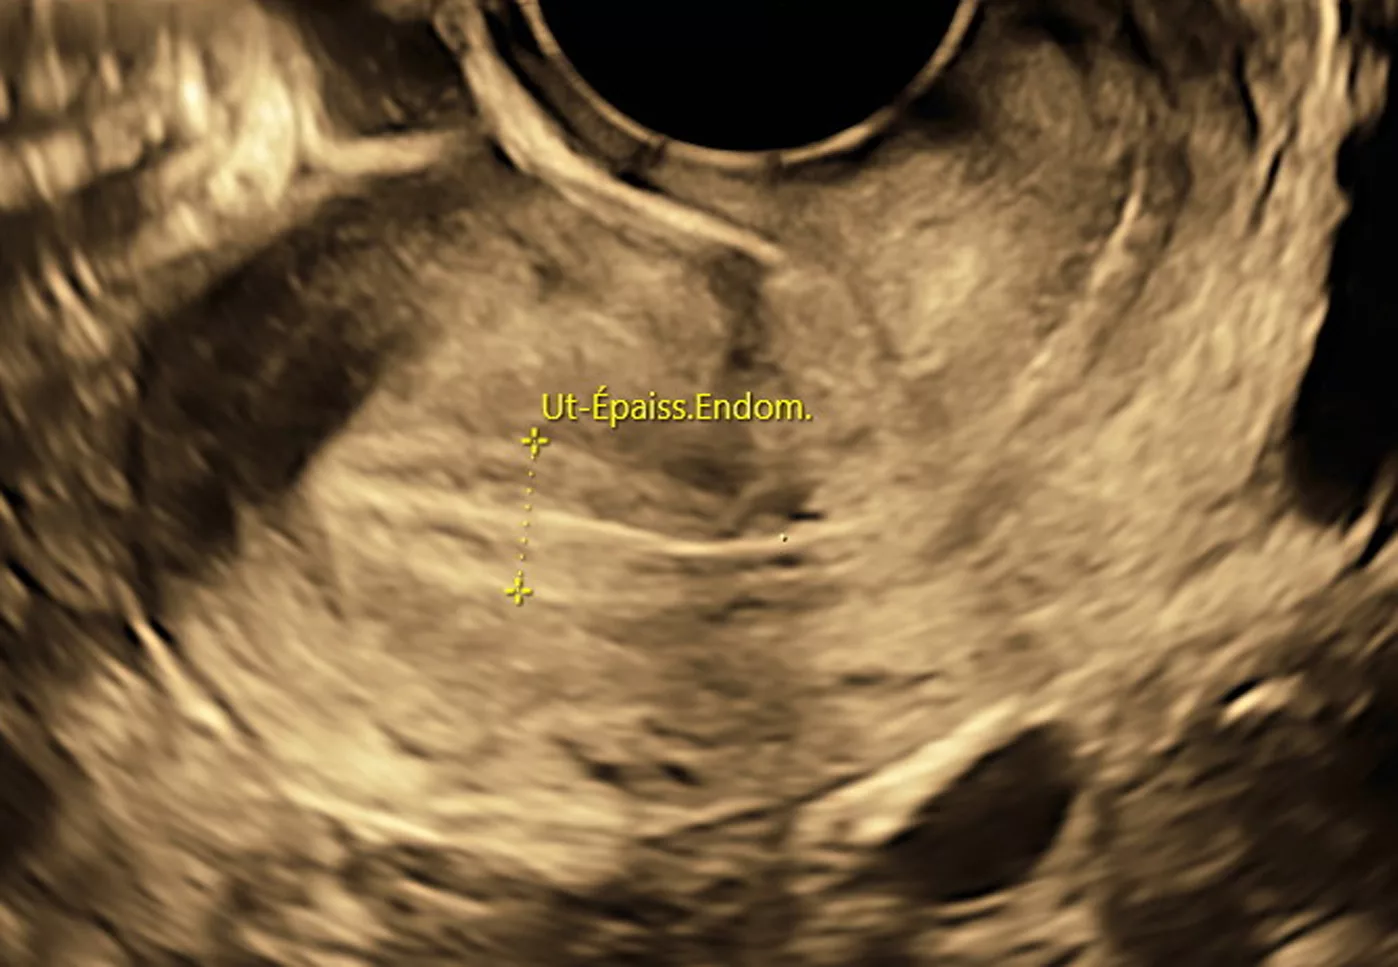

L’Échographie par voie endo-vaginale

Nécessite votre consentement explicite et absolu avant de pouvoir être pratiqué.

L’examen ne doit pas être douloureux.

Sera réalisé dans le respect de l’intégrité physique et morale de la patiente.

Signaler au praticien tous facteurs ou toutes raisons pouvant rendre l’examen désagréable.

L’examen pourra être interrompu à votre demande et sans que vous n’ayez besoin de vous justifier à n’importe quel moment.

Si vous n’avez jamais eu de rapport sexuel, l’examen sera réalisé par voie abdominale.